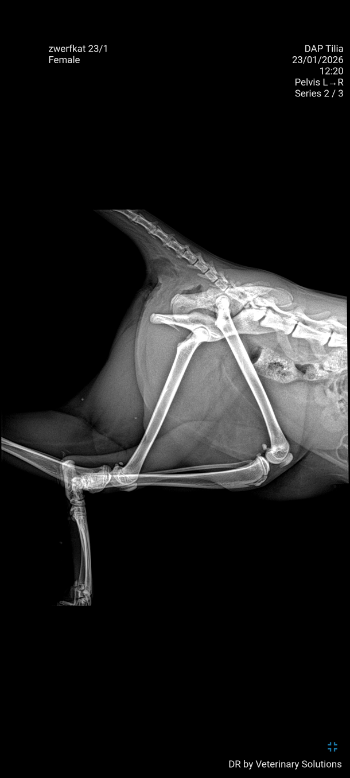

Bij nazicht door de dierenarts werd gevonden dat ze een ernstige breuk in haar bekken had opgelopen, waardoor de twee helften nu los van elkaar staan. Ook blijkt ze twee haakjes in haar maag te hebben 😔. Maar dit kleine vechtertje toonde zich van haar sterkste kant en probeert ondanks de pijn om rond te lopen en op de kattenbak te gaan, ook al gaat dat moeizaam 💪.

Er werd contact opgenomen met de orthopedist om te opties te bespreken. Ze zou een operatie moeten ondergaan waarbij haar bekken terug aan elkaar wordt gezet. Gezien haar vechtlust, willen wij haar die kans ook zeker geven 😻. Dus hebben we de operatie ingepland voor dinsdag.